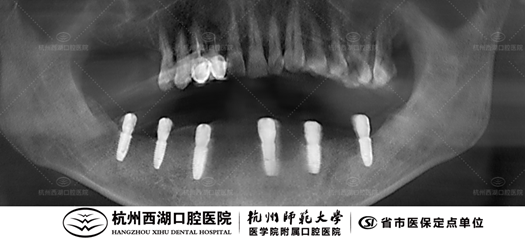

术前CBCT照如下

术后CBCT照如下

种植团队采用All-on-6即刻修复技术,为江叔叔植入6颗种植体,即日戴牙完成半口修复,好牙一日得!